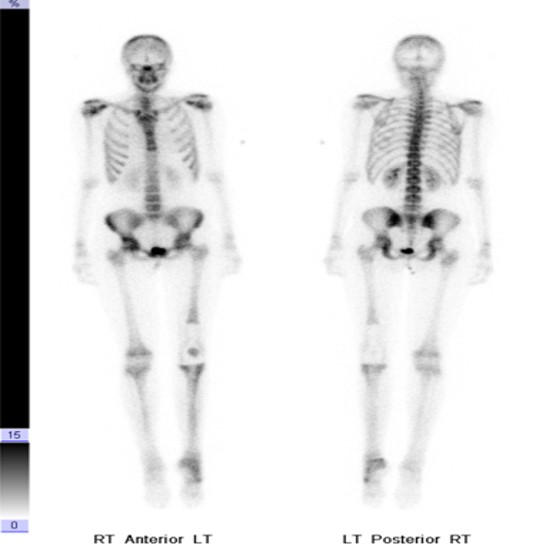

Normal whole body pediatric and adult bone scintigraphy with technetium 99m methylene diphosphonate (MDP) display different features (figure 1). In the pediatric population there is intense radiotracer uptake in the growing physes of long bones. Normal adult whole body planar bone scans with Tc-99m MDP demonstrates normal expected uptake in the bilateral sacroiliac joints, iliac crest, acromioclavicular joints, sternoclavicular joints, and nasal region. Normal radiotracer activity is excreted into the kidneys and urinary bladder.

| Normal pediatric whole body Technetium 99m-methylene diphosphonate (Tc-99m MDP) bone scan displays intense expected radiotracer uptake in the physes of long bones. |

Normal adult whole body bone scan Tc-99m MDP demonstrates normal expected uptake in the bilateral sacroiliac joints, iliac crest, acromioclavicular joints, sternoclavicular joints and nasal region. Normal radiotracer activity is excreted into the kidneys and urinary bladder. |